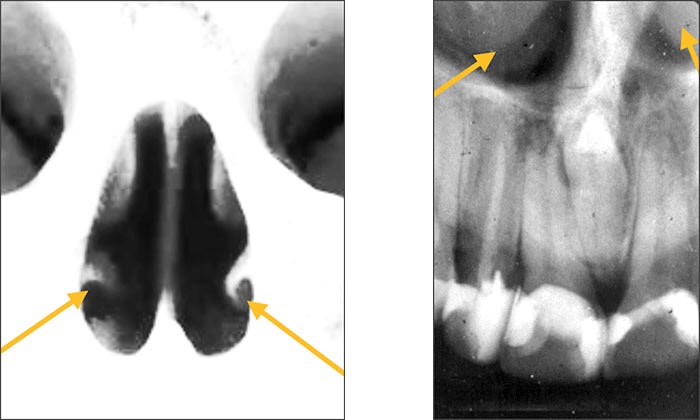

• Nasal fossa – The nasal fossae are the nasal openings located above the maxillary anterior teeth. Radiographically, the nasal fossae appear as vertically oblong radiolucent structures bounded by bone.

• Anterior Nasal spine – Located at the anterior & inferior portion of Nasal cavity situated in the midline. Appears as a V-shaped or triangular radiopacity.

• Nasal Septum – Vertical bony wall that divides the nasal cavity into right & left fossae formed by Vomer & ethmoid bone.

• Inferior concha – Appears as diffuse radiopaque mass within nasal cavity.

• Nasal cavity – Pear shaped, air filled conpartment of bone located superior to maxilla, appears as radiolucent area.

• Incisive foramina – Nasopalatine vessels & nerves lies in midline on lingual aspect of hard palate. Radiographically, it appears between the roots of the central incisor teeth as a round to oval radiolucency less than one centimeter in diameter.

• Floor of nasal cavity – Bony wall formed by palatal process of Maxilla & horizontal portion of palatine bone. Appears as dense radio-opaque band that cuts the maxillary process.

• Y line of Ennis – The inverted Y is a radiographic landmark that depicts where the nasal fossa crosses the maxillary sinus. The boundary between them is shaped like an upside-down letter Y, hence its name.